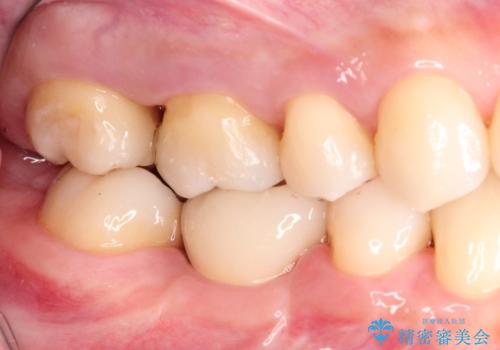

むし歯の治療。ゴールドインレーによる修復

ゴールドインレーは適合が良く、割れることもないため、長期的に安定した治療法となります。

- インレーおよびクラウンは脱離するリスクがあります

- 形成量はセラミックより少ないですが、歯の形成、修復後に歯に症状が出ることがあります